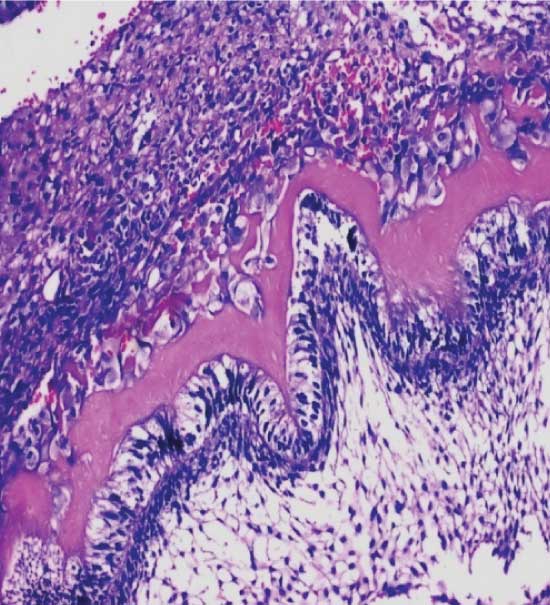

Our case presented clinical and radiographic patterns in accordance to the literature, since a radiographic examination could confirm the slow-growing character of the disease, as well as, the progressive production of calcifying material by the tumour. Histologically, AFO is composed of strands, cords and islands of odontogenic epithelium embedded in a cell-rich, primitive ectomesenchyme that resembles the dental papilla [Table/Fig-4 & 5]. Dentin and enamel matrix are also seen [Table/Fig-6]. Recently, it was determined that amelogenins participate in multi-faceted aspects of dental hard tissue formation that takes place in AFO [Table/Fig-7] [12].

Under scanner view (4X) the H&E section shows odontogenic islands with in the ectomesenchymal tissue

Under low power magnification (10X) shows induction effect of odontogenic epithelium and the formation of dental hard tissue

Under high power magnification (40X) shows ameloblast like cells with dental hard tissueformation